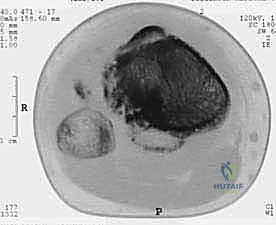

يُعد استئصال الظنبوب القريب بالطرف الصناعي إجراءً جراحياً متقدماً ومعقداً للغاية، يتضمن إزالة دقيقة للجزء العلوي من عظم الساق (الظنبوب) المصاب بورم خبيث، أو ورم حميد عدواني، أو تلف مفصلي مدمر لا يمكن إصلاحه بالطرق التقليدية. بعد الاستئصال الآمن للورم مع حواف أمان سليمة، يقوم الجراح باستبدال العظم والمفصل المفقود بطرف صناعي معدني متطور (مصنوع غالباً من التيتانيوم وسبائك الكوبالت والكروم) لاستعادة وظيفة الركبة والطرف السفلي، مما يتيح للمريض العودة إلى ممارسة حياته الطبيعية والمشي على قدميه مجدداً.

تُعتبر منطقة الظنبوب القريب (Proximal Tibia) واحدة من أكثر المواقع التشريحية تحدياً في جراحات العظام والأورام. يعود هذا التعقيد إلى عدة عوامل: قربها الشديد من حزمة الأوعية الدموية والأعصاب الرئيسية التي تغذي الساق والقدم، ونقص التغطية العضلية الكافية في الجزء الأمامي من الساق، بالإضافة إلى الدور الحيوي الذي يلعبه هذا الجزء في آلية تمديد الركبة (Extensor Mechanism) وتحمل وزن الجسم بالكامل. لذلك، فإن نجاح هذه الجراحة لا يعتمد فقط على المعدات الحديثة، بل يعتمد بشكل أساسي وحاسم على مهارة الجراح وخبرته الاستثنائية.